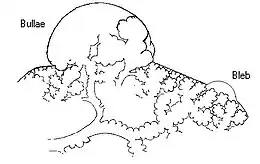

Paraseptal

Paraseptal emphysema, also called distal acinar emphysema, relates to emphysematous change next to a pleural surface, or to a fissure.[18][27] The cystic spaces known as blebs or bullae that form in paraseptal emphysema typically occur in just one layer beneath the pleura. This distinguishes it from the honeycombing of small cystic spaces seen in fibrosis that typically occurs in layers.[27] This type of emphysema is not associated with airflow obstruction.[28]

Bullous

When the subpleural bullae are significant, the emphysema is called bullous emphysema. Bullae can become extensive and combine to form giant bullae. These can be large enough to take up a third of a hemithorax, compress the lung parenchyma, and cause displacement. The emphysema is now termed giant bullous emphysema, more commonly called vanishing lung syndrome due to the compressed parenchyma.[29] A bleb or bulla may sometimes rupture and cause a pneumothorax.[17]

Focal emphysema is a localized region of emphysema in the lung that is larger than alveoli, and often associated with coalworker's pneumoconiosis.[41] This is also known as localized pulmonary emphysema.[42] Blebs and bullae may also be included as focal emphysema. These can be differentiated from the other type of enclosed air space known as a lung cyst by their size and wall thickness. A bleb or bulla has a wall thickness of less than 1 mm, and are smaller.[43]